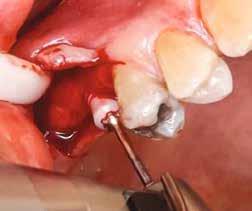

Helyi érzéstelenítést végeztünk a műtéti területen artikain és 1:100 000 adrenalin segítségével. A recipiens területet előkészítettük, élesen disszekciót végeztünk, hogy egy izomtapadástól mentes periosteum ágyat képezhessünk. Ettől disztálisan két párhuzamos parakresztális metszést végeztünk egy 15C-s szikepengével, majd a metszéseket egy

2–5. ábra: A metszések és a deepitelizáció. – 6–9. ábra: Félvastag lebeny. – 10. ábra: A nyelezett ínylebeny „bepróbálása”.

horizontális metszéssel kötöttük össze (2–5. ábra). A metszések hosszát és a köztük lévő távolságot minden esetben a lágyszövet augmentációhoz szükséges keratinizált szövet határozza meg. A lebeny deepitelizációját egy 15C-s szikepengével végeztük (6. ábra). Ezt követően félvastag lebenyt preparáltunk (7. ábra). A lebenyt apikálisan, az alapjáról belső, felületes metszéssel felszabadítottuk, hogy passzívan áthelyezhessük és rögzíthessük, feszülés nélkül. Meziális irányba 180 fokkal átforgattuk (8–9. ábra). A meziális papillát alagúttechnikával (tunnelling technique) készítettük elő a graft befogadására (10. ábra). Az így kialakított lebenyt a recipiens ágyban rögzítettük az újonnan kialakított vesztibulum alapjánál 5-0 nem felszívódó PTFE (Coreflon, IMPLACORE) varratokkal. A graftot behajtottuk az ínyszél alá és meziális oldalon rögzítettük PTFE varratokkal (11–14. ábra)